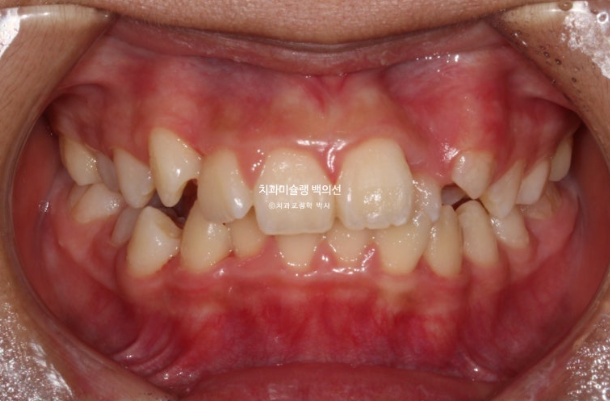

24년 1월 교정치료를 위해 온 만 10세 어린이입니다.

24.02

3년 전에 소아치과에서 앞니 부분교정을 한 적이 있다고 합니다.

그래서 위 앞니에는 중절치 두 개를 잇는 철사유지장치가 붙어있었습니다.

중심선이 약 2mm 어긋나 있고 위 앞니 치축은 한쪽으로 기울어져 있습니다.

앞니가 깊게 물리는 과개교합도 보입니다.

공간부족으로 인한 덧니가 심해 반대교합이 있습니다.